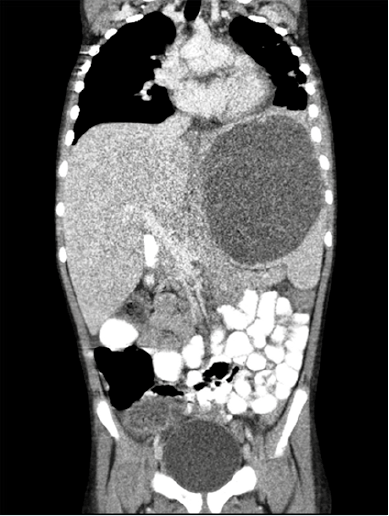

suplementario. Ante la confirmación ecográfica del aumento del tamaño de la colección líquida intraesplénica y hepatización del lóbulo inferior izquierdo pulmonar, se decidió una tomografía computada (Figura 3) para definir la localización exacta de la lesión y su relación con las estructuras vecinas. Se volvió a drenar guiándose con control ecográfico y se programó para capsulectomía definitiva. En la intervención se encontraron una lesión grande encapsulada en la región anterior del bazo, en relación directa con el ligamento gastrocólico y la cúpula vesical, de contenido mixto purulento-sanguinolento. Se efectuaron la extirpación quística parcial y la fenestración de la cápsula. El análisis anato mopatológico de la pieza fue compatible con quiste epitelial primario.

En el diagnóstico de los quistes esplénicos, complicados o no, los mayores avances se han conseguido en radiología y medicina nuclear; la ecografía y la tomografía computada son las pruebas diagnósticas de elección, con una sensibilidad superior a 90%.11 Ambas técnicas permiten caracterizar la lesión (componente hemorrágico, tejido graso, etc.) y estudiar su tamaño y relación con las estructuras adyacentes, información muy útil en el diagnóstico diferencial y tratamiento. La ecografía también es útil para guiar los procedimientos de aspiración del quiste y en el seguimiento conservador de la enfermedad. La tomografía computada, según gran parte de los protocolos, es útil antes de cualquier procedimiento quirúrgico para indicar el mejor sitio de acceso e inferir si es posible la esplenectomía parcial.12